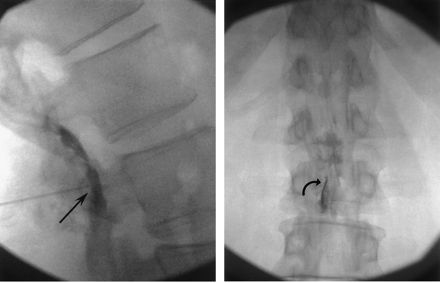

In 55 of 74 LESI procedures (74.3%), air pressure resistance was first lost upon appropriately entering the lumbar posterior epidural space. Confirmation of tip position was made with nonionic contrast medium injection and anteroposterior and lateral epidurogram and correct position was clearly recognized in these patients (Fig 3 A and B).

A and B, Lateral and anteroposterior fluoroscopic images of a 56 year-old-man with back and leg pain during LESI procedure demonstrates proper position of the needle tip after initial loss of resistance in the posterior epidural space in the lateral (arrow) and anteroposterior (curved arrow) projections.